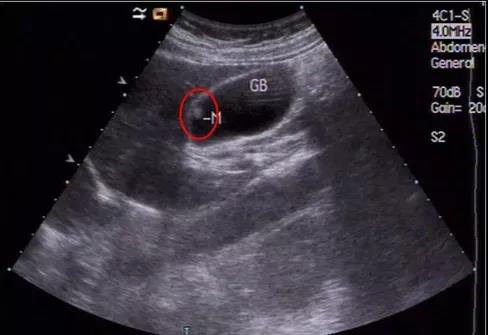

①看真假:真正可能變癌的是真息肉,假息肉不用管;

②看大小:長到1厘米了就需要考慮手術(shù),風險大了;